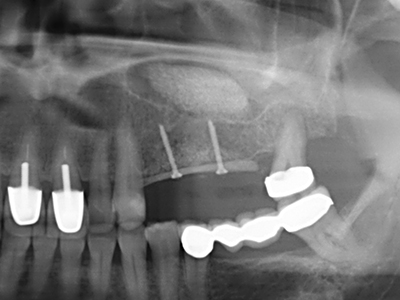

Indication: Preparation near nerves

As noted above, indications for piezosurgery can also be found in the field of conservative dental surgery. Special working tips simplify the exposure of root tips and make it easier to protect nerves and sinus mucous membranes, particularly in the lower premolar and upper posterior tooth regions. Angled diamond tips are used to precisely prepare the resection cavity for the retrograde root filler material for unsealed apical obturation. The ultrasonic technology means the tips can be very slender, which improves the view and the size of the access cavity. As a result, the application of ultrasonic surgery for this indication is one of the standard procedures for apical resection (Del Fabbro, Tsesis et al. 2010, Scarano, Artese et al. 2012).

Indication: Apical resection

When surgical procedures are performed on bone in the immediate vicinity of sensitive structures such as blood vessels or nerves, rotary instruments pose a significant risk of iatrogenic injury. Piezoelectric devices can be helpful for preparation of bone covers and removal of hard tissue close to nerves, particularly for exposure of nerves after iatrogenic injury but also during nerve lateralization for resective and reconstructive procedures or implant placement (Fig. 17-20). Light contact between the piezotip and the nerve does not generally result in damage but proceeding incautiously with saw-like motions or attachments where a residual bone substrate remains may cause temporary or even permanent nerve damage. However, the risk of damage is considered to be substantially lower than when using saws or milling instruments (Pereira, Gealh et al. 2014).